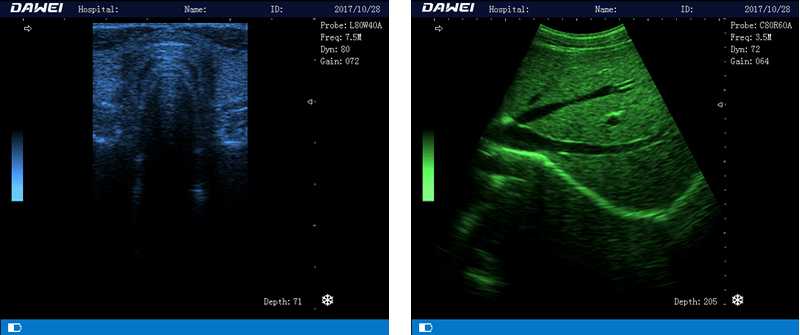

DW-580

筆記本全數字超聲診斷儀

1.優質的數字成像技術,圖像更清晰